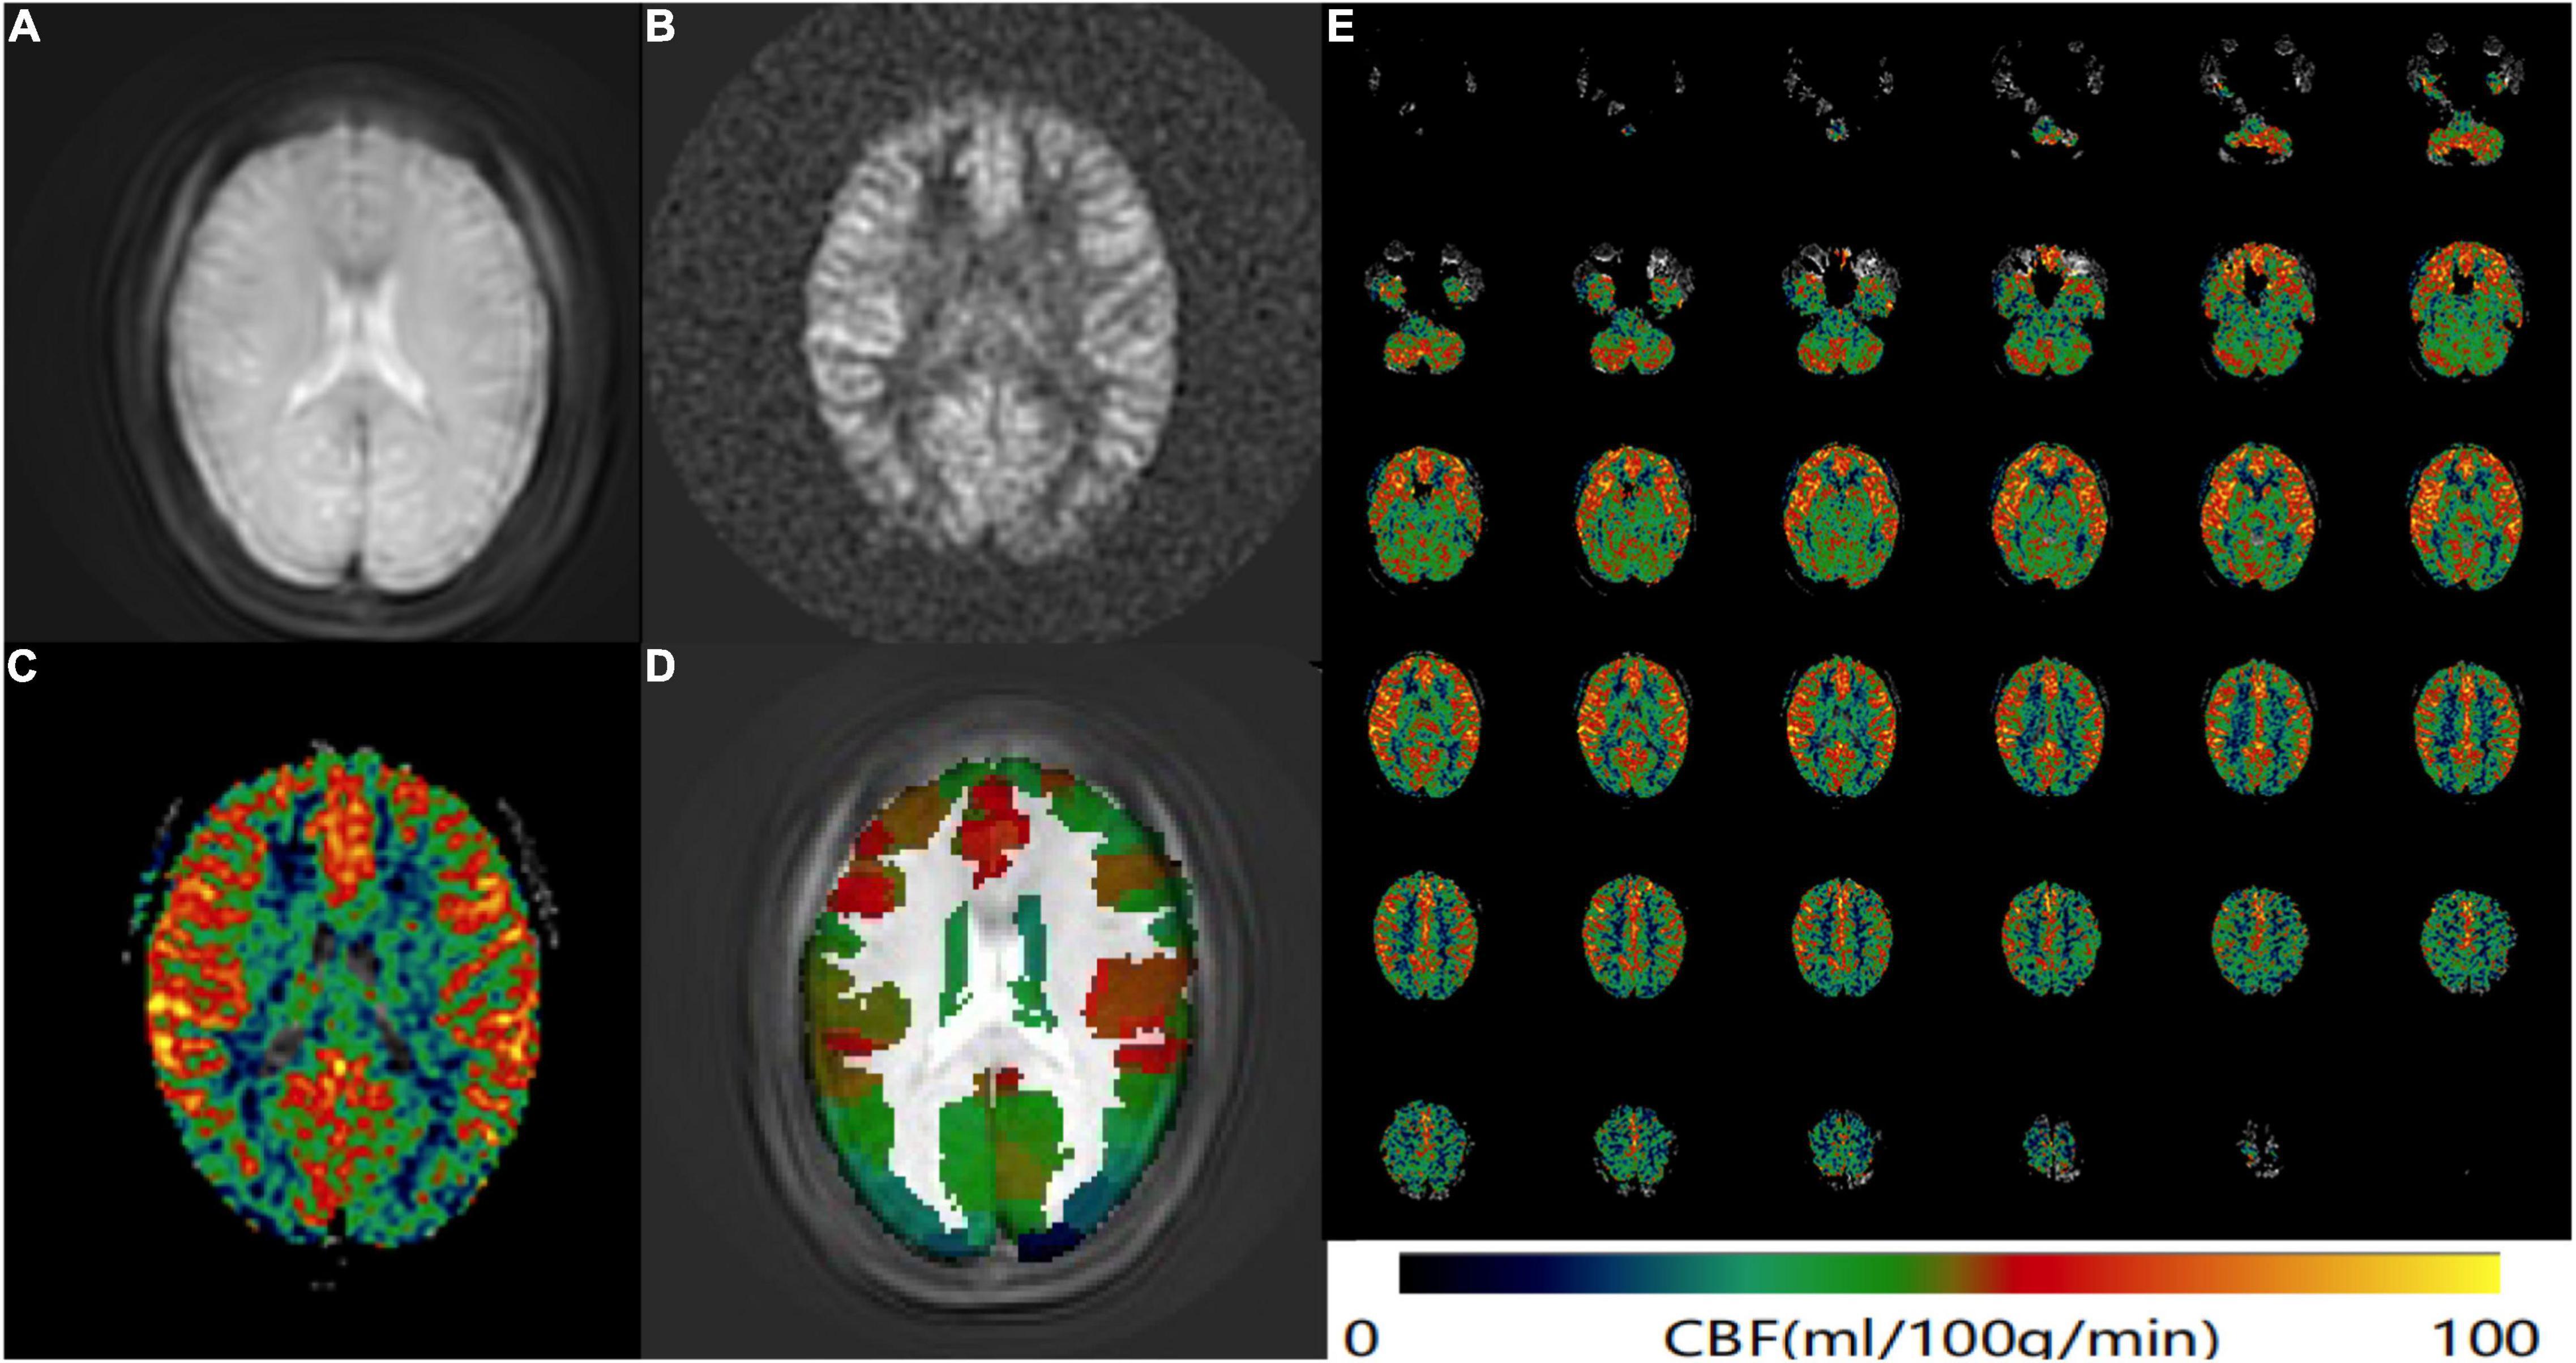

CereFlow software (An-Image Technology Co., China) was used to process ASL data, the steps were as follows: (1) convert the 3D ASL perfusion weighted images and proton density images (generated from GE MR scanner) into the CBF map of cerebral perfusion for each subject by using the simplified one compartment model (St Lawrence and Wang, 2005). (2) normalize the CBF map to the Montreal Neurological Institute (MNI) space with intensity-based image registration where the MNI152 brain template was used as a fixed image, and transform each subject’s image as the motion image to match the fixed image. (3) then the Brainnetome Atlas (BNA) (Fan et al., 2016) was overlaid. (4) the average CBF value of each brain region from BNA was finally obtained (Figure 1).

Figure 1. ASL data processing workflow. Convert the (A) 3D ASL proton density images and (B) perfusion weighted images into the CBF map of cerebral perfusion for each subject. (C) The CBF map was normalized to the MNI space and then the BNA was overlaid. (D) The average CBF value of each brain region from BNA was obtained. (E) An example CBF map of a female SSNHL patient calculated by Cereflow software.